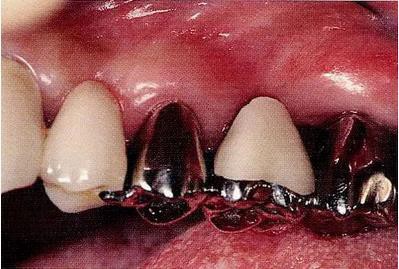

圖18-1 左下六近中根的遠(yuǎn)中部多會(huì)形成concave(凹面),一旦這種部位在口腔內(nèi)露出,對(duì)菌斑控制就會(huì)非常困難。

▼圖18-2

圖18-2 拔除近中根的牙齒遠(yuǎn)中面。

▼圖18-3

圖18-3 在其他醫(yī)院進(jìn)行了的修復(fù)處理。拔除了第一磨牙遠(yuǎn)中根的病例。近中根遠(yuǎn)中面殘留著一部分的邊緣。在這種部位很容易滯留牙垢,菌斑的控制會(huì)也很困難。